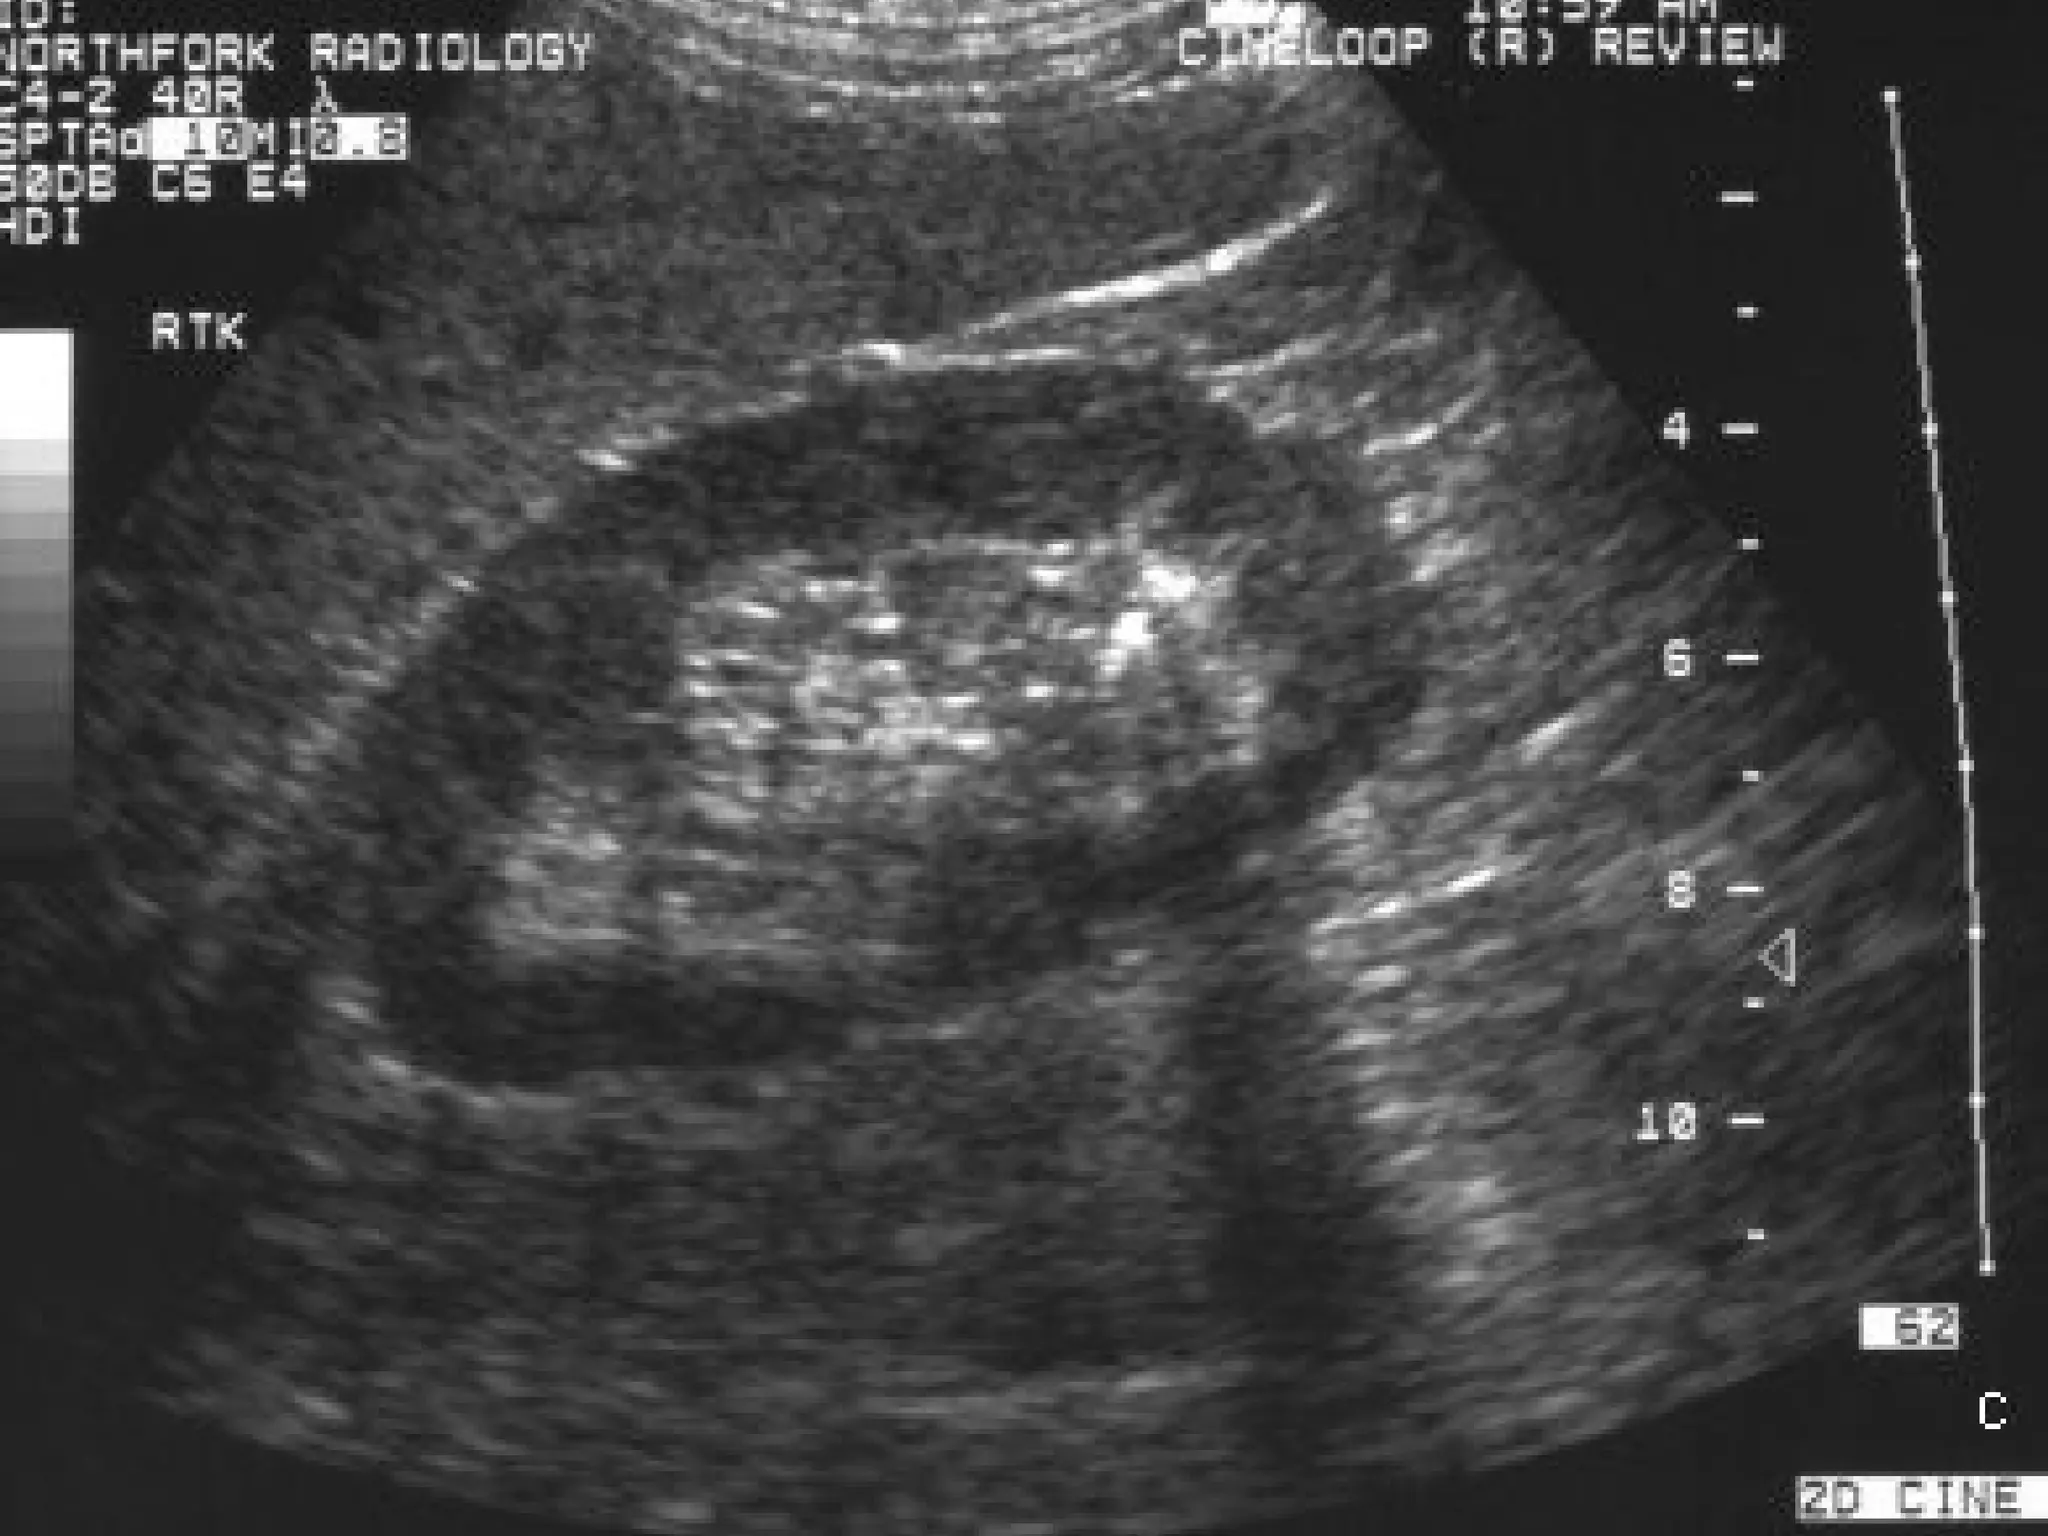

This is why the gold standard is the non-contrast CT scan. It’s fast, and it shows exactly where the stone is and how big it is. If you're pregnant or trying to avoid radiation, they’ll go with an ultrasound, though it’s a bit less precise for tiny stones.